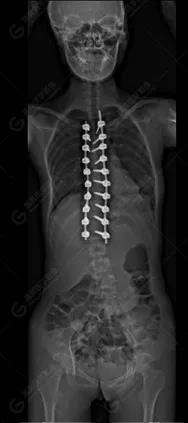

15歲女性,發(fā)現(xiàn)特發(fā)性脊柱側(cè)彎3年,于2019年1月23日來(lái)到廣東高尚醫(yī)學(xué)影像診斷中心行EOS檢查,2019年2月行手術(shù)治療后多次到中心行EOS復(fù)查。

2019-02-01

脊柱側(cè)彎最重要一個(gè)臨床參數(shù)是側(cè)彎角(Cobb角),目前臨床公認(rèn)的Cobb角>10 °診斷為脊柱側(cè)彎;如Cobb角進(jìn)行性持續(xù)性增加>40 °需要手術(shù)矯正治療。

本例患者胸椎右側(cè)彎,Cobb角(T6/T12)為47°,遂行手術(shù)矯正治療。術(shù)后多次隨訪的Cobb角(T10/L3)為12°-15°之間,較術(shù)前明顯縮小。